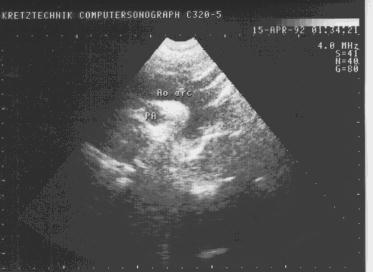

Данный доступ используется для визуализации дуги аорты, перешейка аорты и нисходящего отдела аорты. Дуга аорты огибает правую ветвь легочной артерии (рис.11).

Надгрудинная проекция дуги аорты.

Рис.11

Надгрудинная проекция

дуги аорты.

Ao arc - дуга аорты;

PA - правая ветвь легочной

артерии.